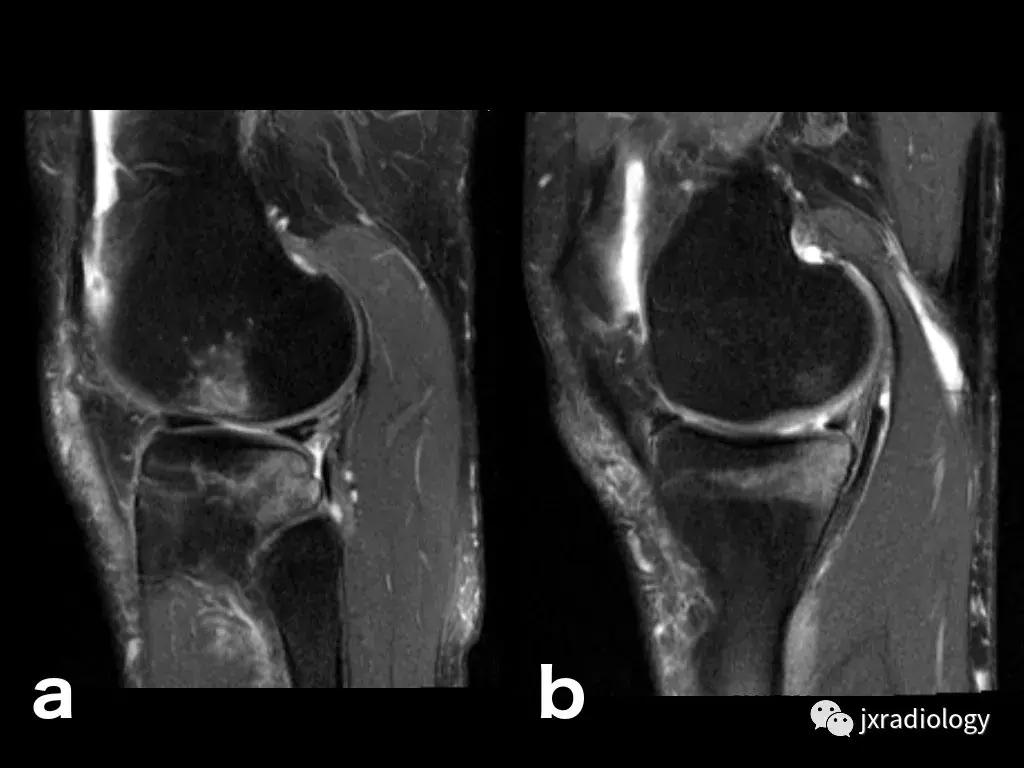

图7:骨小梁骨折:男,15岁;踢足球创伤性事件后的急性疼痛:在T1-WI(a,b)和T2WI-FS上的股骨内侧髁上的低信号微裂纹(c)。在水敏序列(T2-FS-WI)上,骨折周围有明显高信号骨髓水肿。